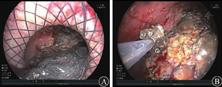

患者入院2周(恢复期)后病情较平稳。2019年10月21日,患者出现发热,体温最高达39.0 ℃,应用美罗培南(0.5 g/次,3次/d)和替加环素(50 mg/次,2次/d)抗感染治疗后,患者体温逐渐恢复至36.5 ℃。2019年10月29日复查CT示胰腺假性囊肿增大,随后患者出现中腹部胀痛、恶心等压迫症状,经多学科讨论后于11月19日行超声内镜引导下经胃胰腺假性囊肿金属支架置入术(图2),术中采集引流液进行细菌培养,等待药敏试验结果期间继续予美罗培南(0.5 g/次,3次/d)和替加环素(50 mg/次,2次/d)抗感染治疗,2019年11月21日(支架置入2 d后)常规行胃镜下经金属支架胰腺坏死组织清除术(图3),术后患者生命体征平稳。2019年11月22日凌晨4:00患者无明显诱因突发呕血,呕吐量约500 mL的鲜红色液体;排暗红色血便1次,量约150 mL;伴心悸、出冷汗,血压为80/50 mmHg,急查血常规示白细胞计数为19.65×109/L,红细胞计数为3.29×1012/L,血红蛋白为105 g/L,急诊CT检查示胰周包裹性积液和积血。急诊胃镜检查示囊肿支架内附着大量血凝块,予拔除金属支架,未见活动性出血(图4),立即行腹腔数字减影血管造影,预防胰大动脉和胰背动脉栓塞,同时予输血和止血等对症支持治疗,患者未再发生活动性出血。

图2 2019年11月19日行超声内镜引导下双头金属支架引流假性囊肿

A 支架释放 B 支架定位(箭头所示)